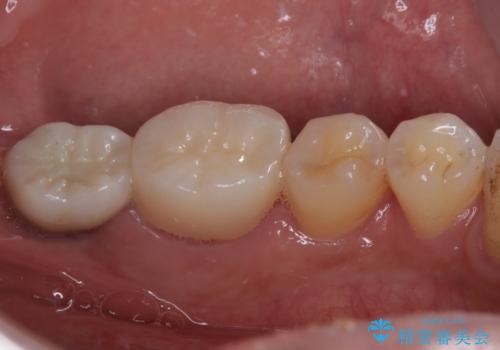

- 左下の歯が欠けてしまったとのことで来院された患者様です。

大きな銀歯が装着されており、その周りからむし歯が広がっている状態でした。

特に症状はなく、神経組織も健全な状態であったため、むし歯を全て取り切った後にフルジルコニアクラウンにて補綴することとしました。